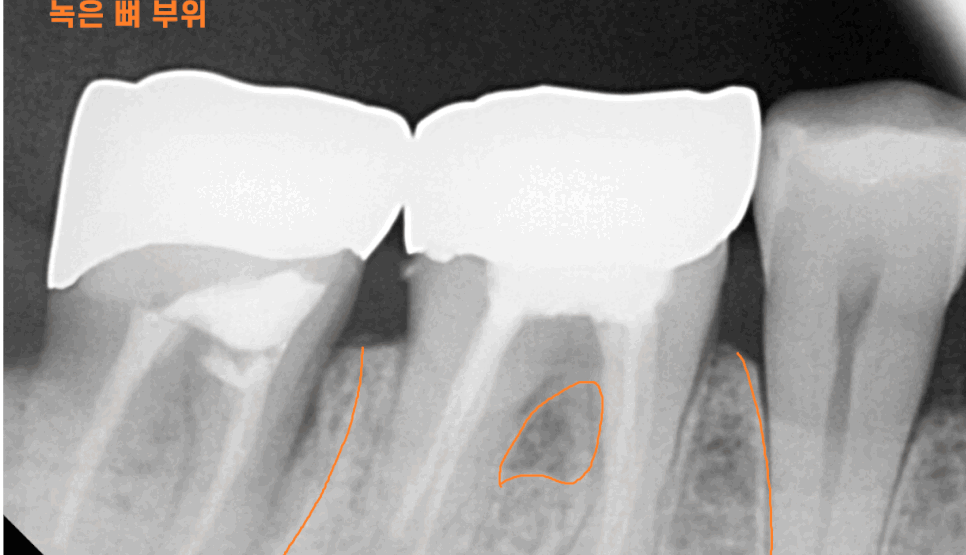

x-ray를 보여드려도 체감을 잘 못하세요~

평면 x ray보다 사실적인

3d ct를 보여드리겠습니다.

뼈는 하얗게 보여야하는데요.

우리가 건강검진 할 때 흉부 엑스레이를 촬영하면

갈비뼈가 하얗게 해골처럼 나오잖아요~

그걸 떠올리면 뼈 = 하얗다

인식이 되실겁니다.

뿌리 염증으로 잇몸뼈를 녹이면

까맣게 변합니다.

뼈가 그만큼 없어지니까요~

치아뿌리 염증 통증은 없더라도 이 염증이 자꾸만 확산되는데

추후 임플란트 치료를 할 때

더 많은 뼈 이식이 필요해요~

당연히 임플란트 예후에도 좋진 않겠죠ㅠㅠ

염증을 제거하고 뼈이식을 하고

공사가 더 커지기도 하고요.